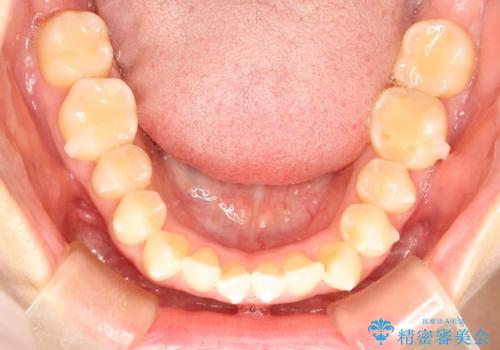

前歯のガタガタをインビザラインで目立たず矯正

- 目立たずに前歯を矯正したいとのことで来院されました。

歯と歯の間にわずかに隙間を作りスペースを確保し、インビザラインにて矯正を行うこととなりました。

前歯の微調整に少し時間がかかりましたが、整った歯並びにすることができました。